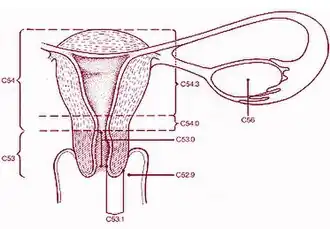

Type 1: Completely ectocervical (common under hormonal influence).

Type 2: Endocervical component but fully visible (common before puberty).

Type 3: Endocervical component, not fully visible (common after menopause).

The cervical canal is generally lined by "endocervical mucosa" which consists of a single layer of mucinous columnar epithelium. However, after menopause, the functional squamocolumnar junction moves into the cervical canal, and hence the distal part of the cervical canal may be lined by stratified squamous epithelium (conforming to a "type 3 transformation zone").[2]